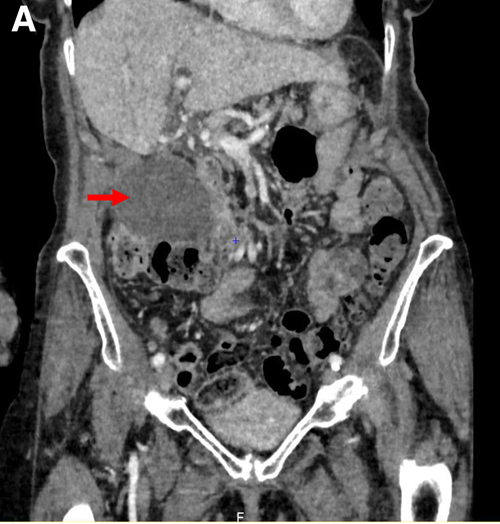

男45岁右季肋区疼痛murphy征阳性b超提示胆囊息肉ct所见如图最可能的